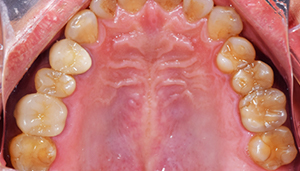

治療前:上の歯

担当医師所見:

臼歯部に残根状態の歯牙があり、またカリエス(虫歯)の散在が認められる。残根部分の両隣在歯は欠損部に対して傾斜し始めている。

治療後:上の歯

左上第1大臼歯は抜歯し、仮歯に置き換えた後治癒を待ちジルコニアBrで補綴。また右上第1大臼歯は根管治療終了後にジルコニアクラウンで補綴。前歯部は審美性を考慮しジルコニアボンドにて補綴した。 色調、形態共に調和がとれている。